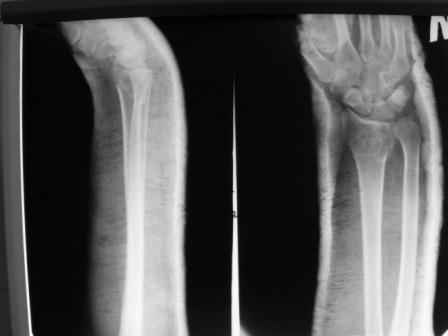

Объективно говоря- снижена высота лучевой кости, диастаз лучелоктевого сочленения, и не

сросся шиловидный отросток. однако на РКТ при сравнении с другой стороной- разница

незначительная.

2. сравнить снимки РКТ (с двух сторон)- так ли велико укорочение лучевой

кости и лучелоктевой диастаз.

3. Ваши мнения, в отношении целесообразности оперативного лечения учитывая ВСЕ вышеизложенное.